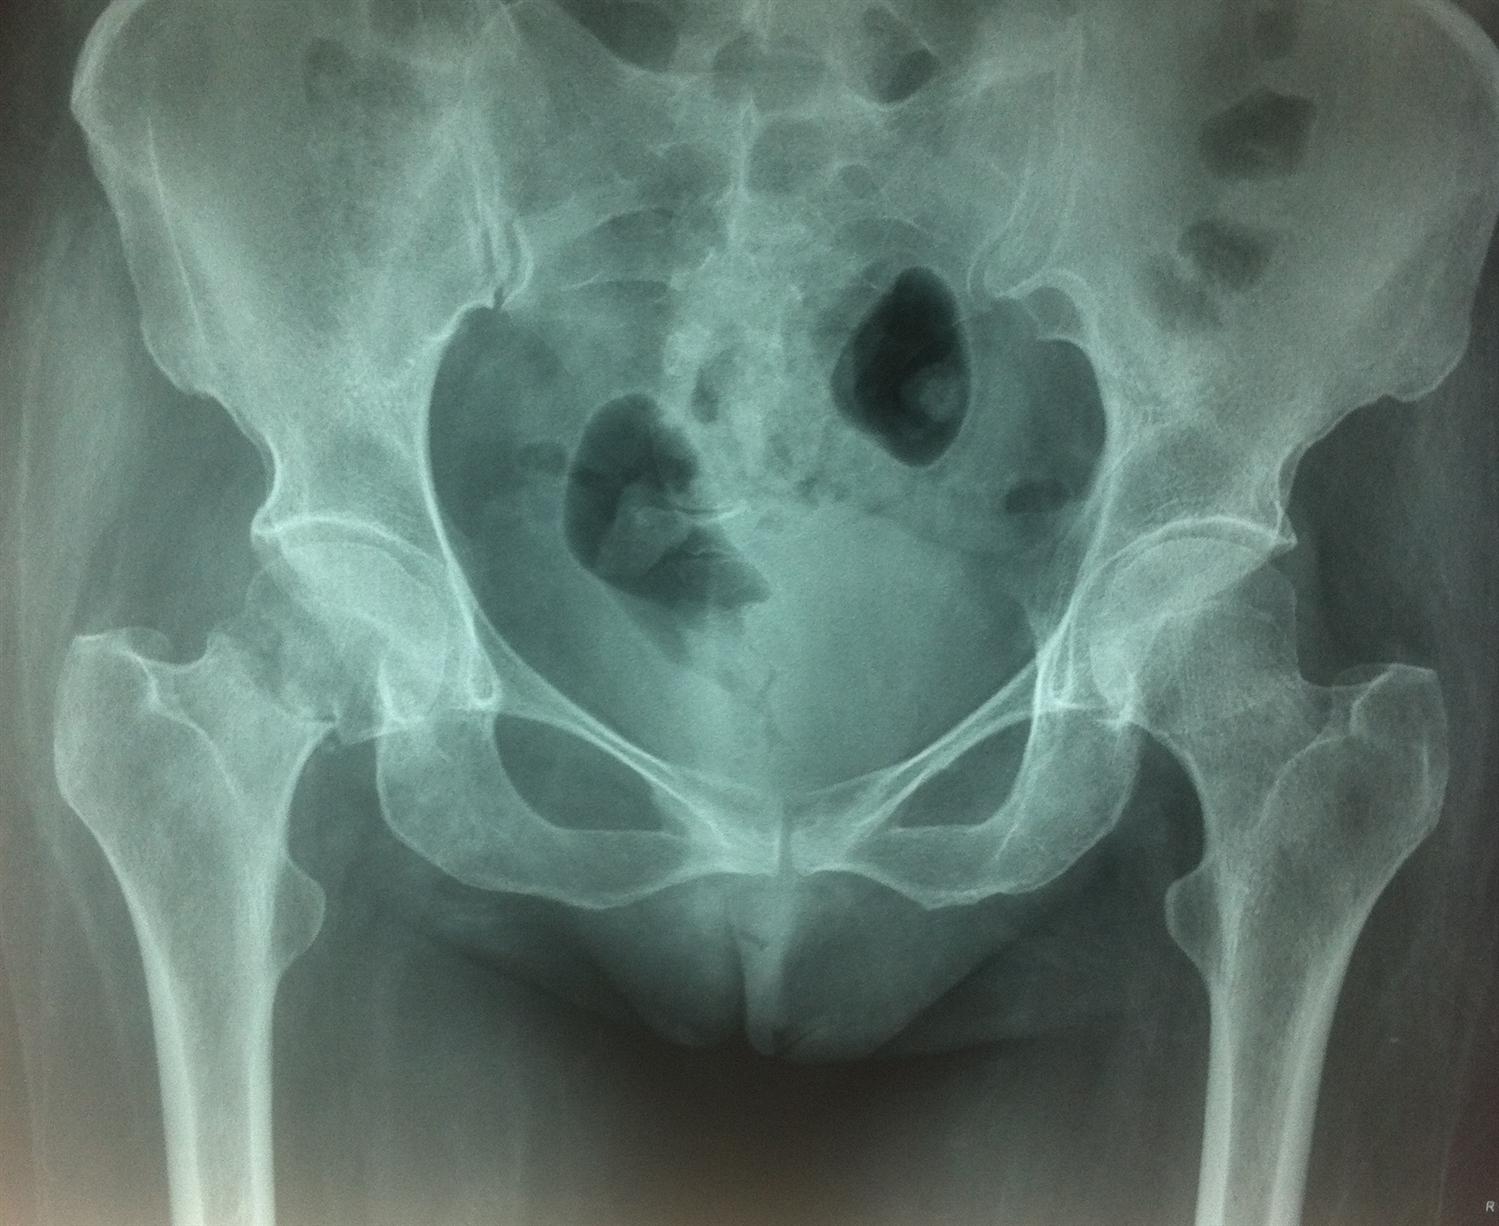

Femoral Neck Fractures Core EM

from coreem.net